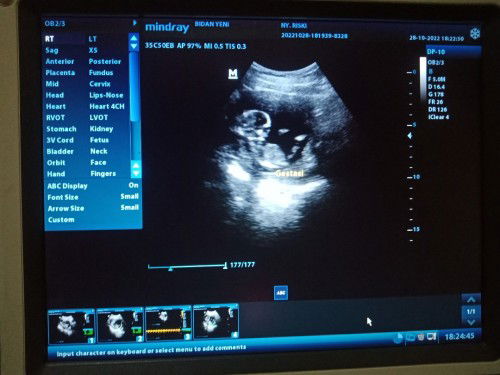

janin nya kan masih kecil bun masih banyak ruang untuk dia muter2 ,. kemarin aku usg malah janin nya lagi tengkurep.

jangan bilang sungsang yahh bunda 😭 bisa dibilang sungsang atau ngga masuk usia kandungan 6 bulan kalau baby masih dipinggir padahal usia 6 bulan dan misal dari vonisan dokter sungsang baru, kalaupun sungsang nanti dokter atau bidan tetap kasih tips ko bun supaya baby di posisinyaa, untuk 14w mah nikmatin aja dulu bun prosesnya, mulmun nyaa, dan yang lainnya bun hehe

Aku usg 15week juga sungsang bund ndapapa masih muda nanti muter2 sendiri kok 🥰

14week itu bukan sungsang, emang janinnya masih muter²